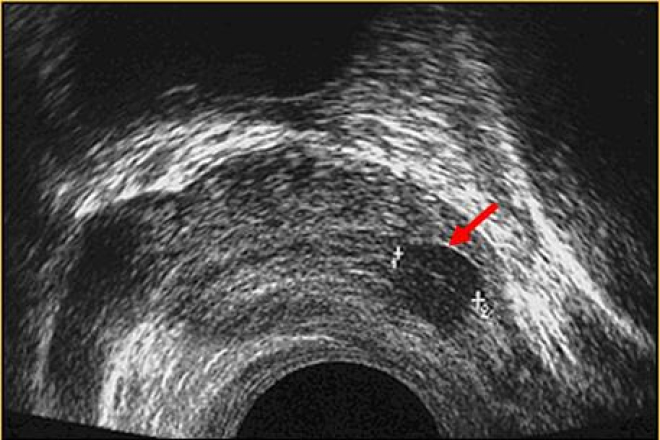

Imágenes hipoecoicas.

Se producen cuando la estructura a estudiar presenta un eco menor que las de su alrededor.